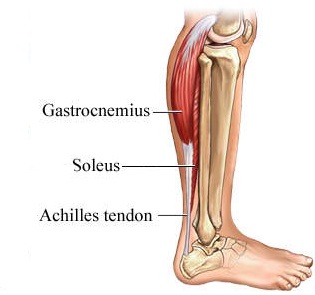

Возможные причины болей в ноге ниже колена и рекомендации